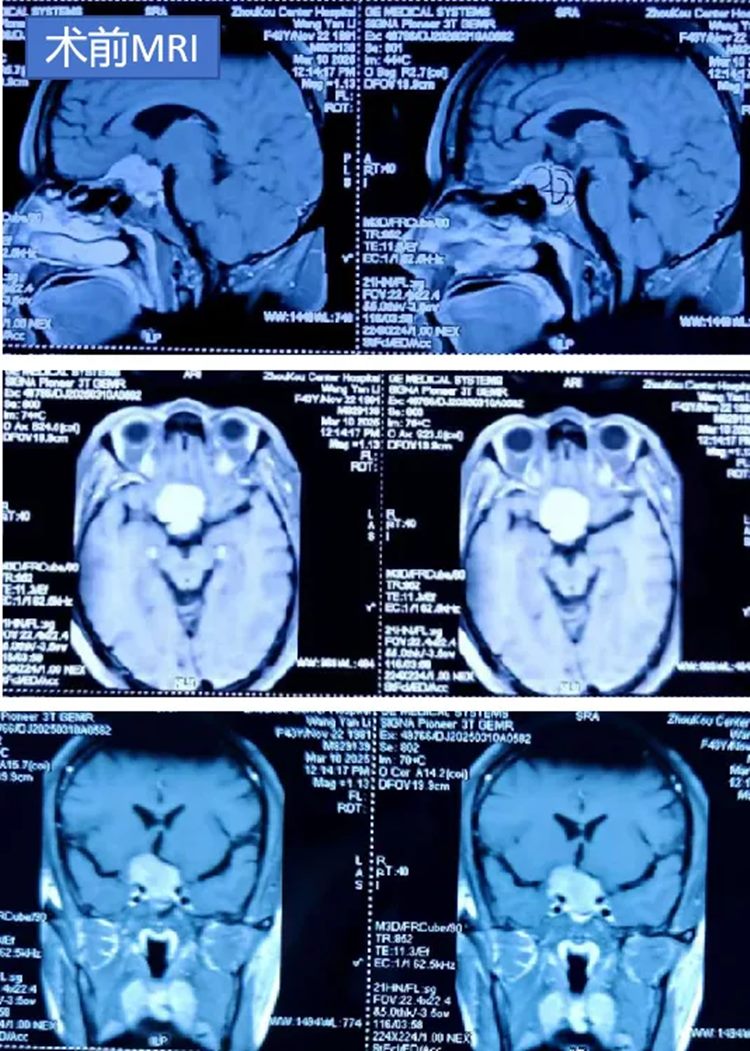

43岁王女士双眼视力持续下降3个月,伴间断头痛,头颅MRI检查发现,她的鞍区有一个占位性病变,考虑为鞍结节脑膜瘤,肿瘤紧贴中线。马建主任团队经周密讨论,选择"额底入路"巧妙避开功能区,2小时完整切除肿瘤。